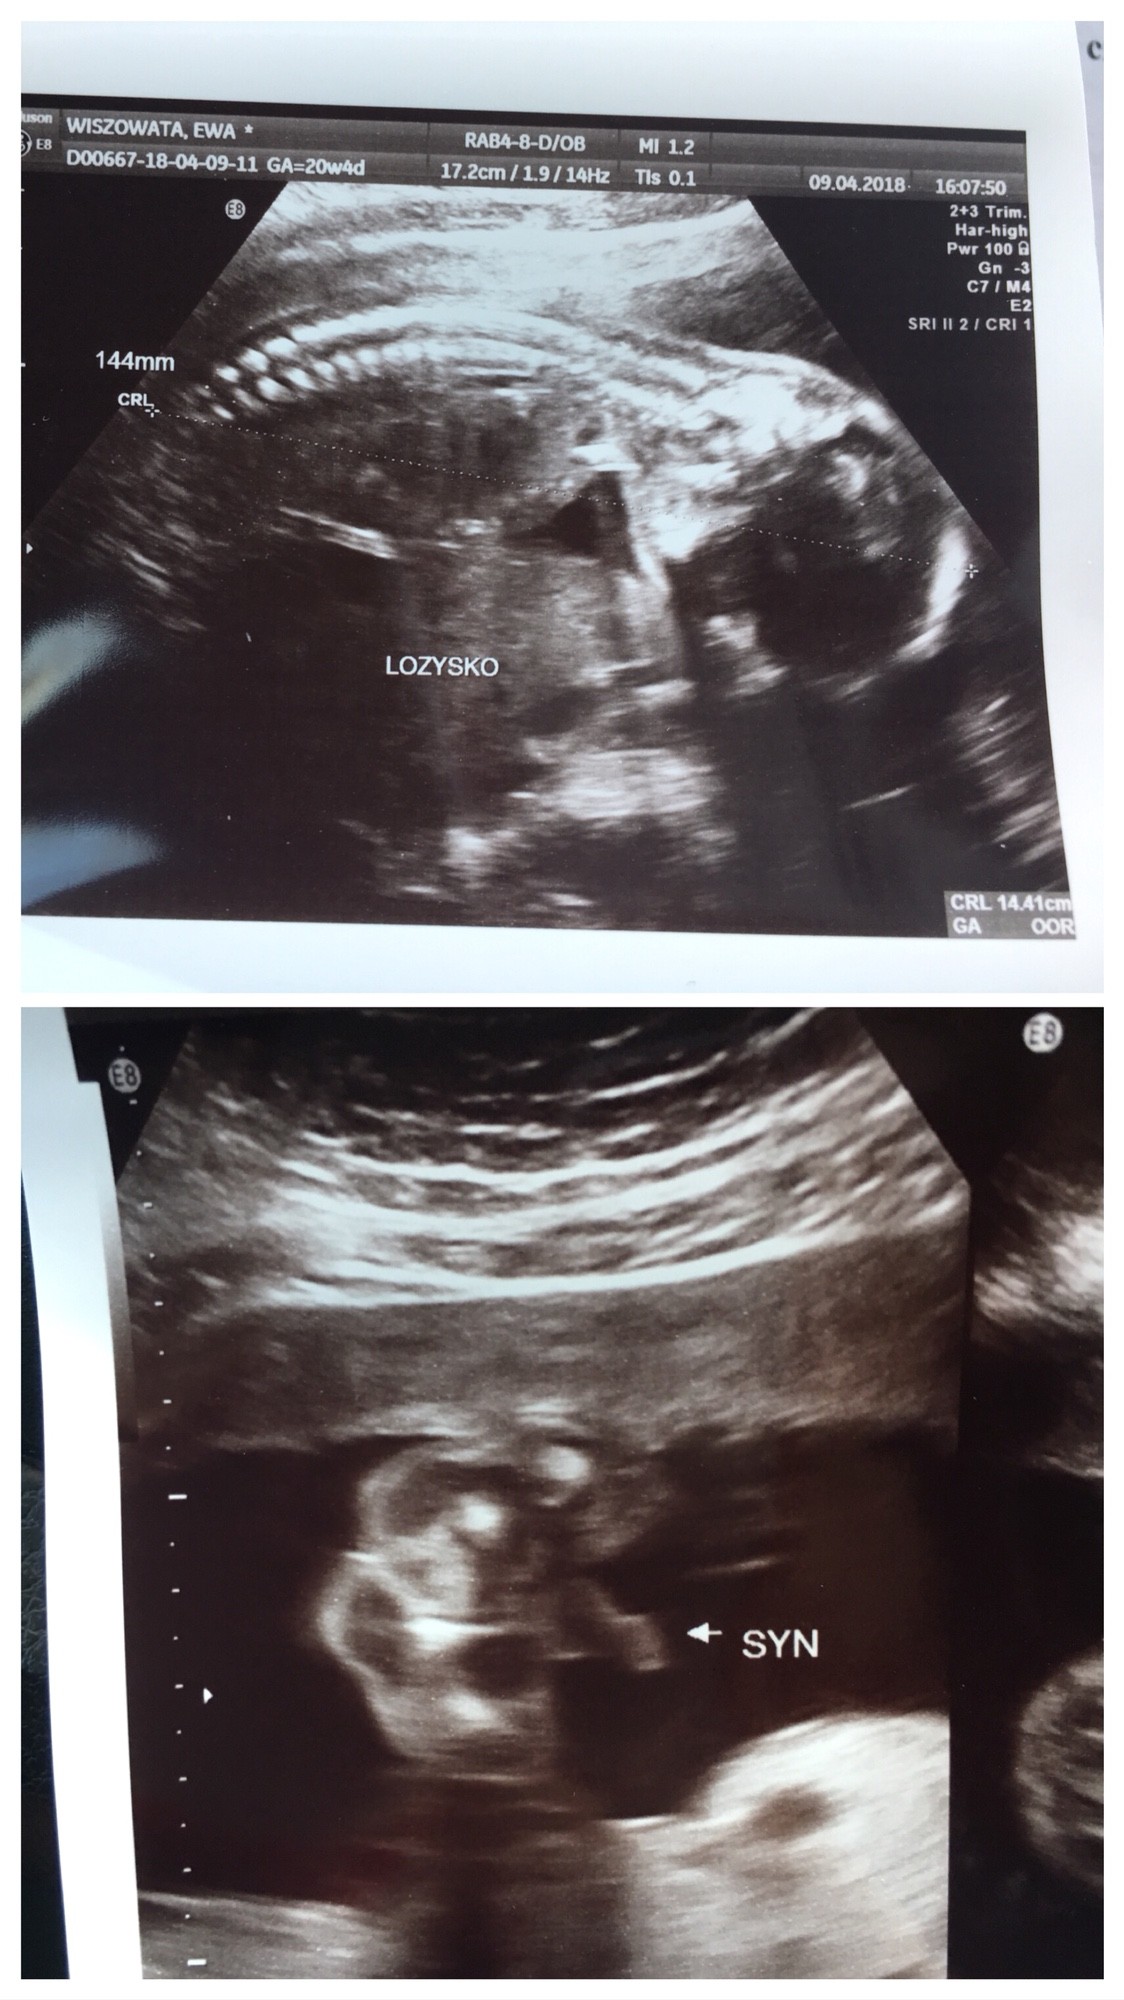

No to genialnie[emoji16] chłopak potwierdzony[emoji16]Oto nasz Kawaler [emoji64] 144mm, 334g i rozwój cały prawidłowyMały leży na brzuszku i trzyma gardę, wiec nie wiemy do kogo jest podobny [emoji12] najważniejsze w każdym razie, ze jest zdrowy [emoji5] Co do płci to pan doktor powiedział, że widzi jajeczka i siureczek i na 100% będzie chłopak!

Mały ułożony podłużnie główkowo i będę rodzić naturalnie. Łożysko na tylnej ścianie. Z dzisiejszego USG wychodzi mi termin porodu na 27.04, więc o tydzień później jak z USG prenatalnego i 4 dni później jak z OM.

A oto i nasz mały Mężczyzna Zobacz załącznik 845224